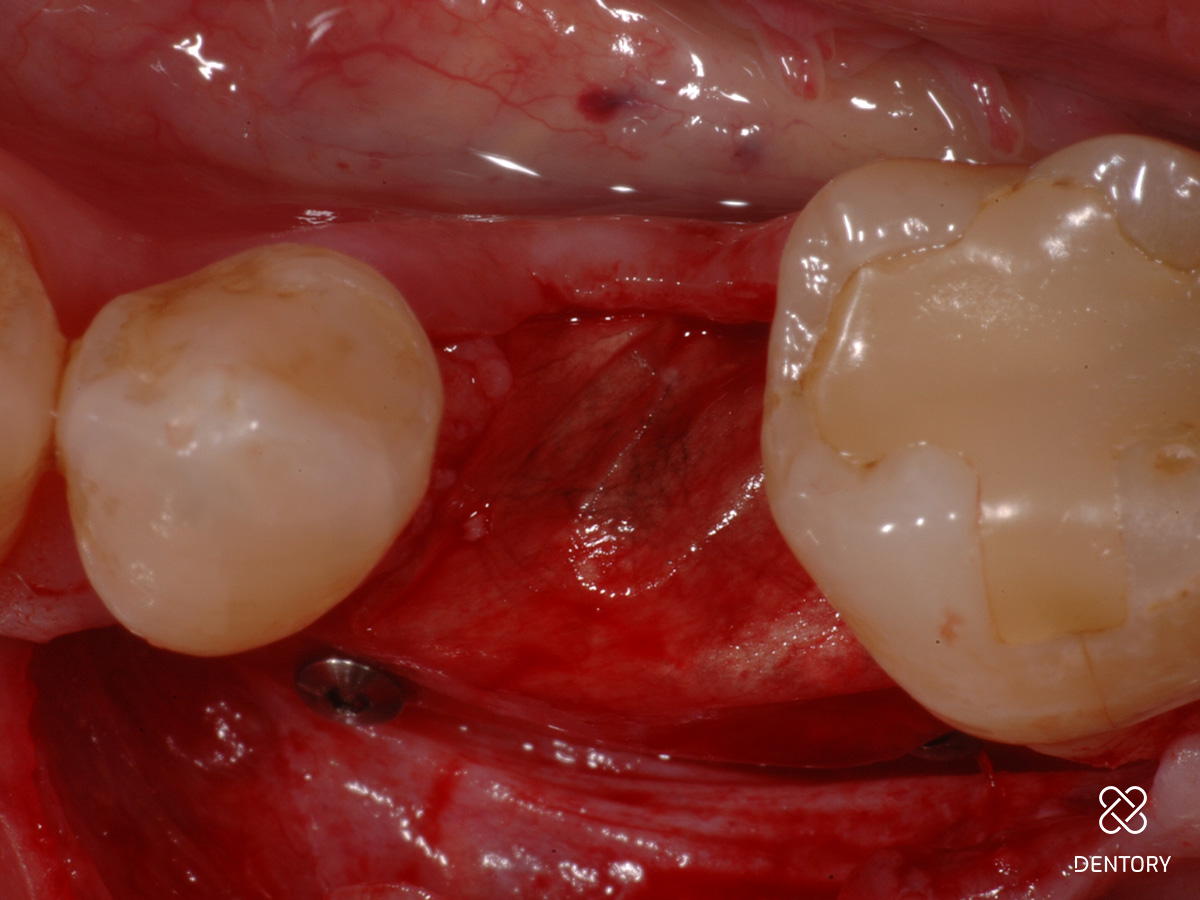

Abbildung 2

Simultane Implantation und GBR: Darstellung des späteren Implantatlagers nach Elevation eines Mukoperiostlappens; es zeigt sich ein horizontal ungenügendes Knochenangebot.